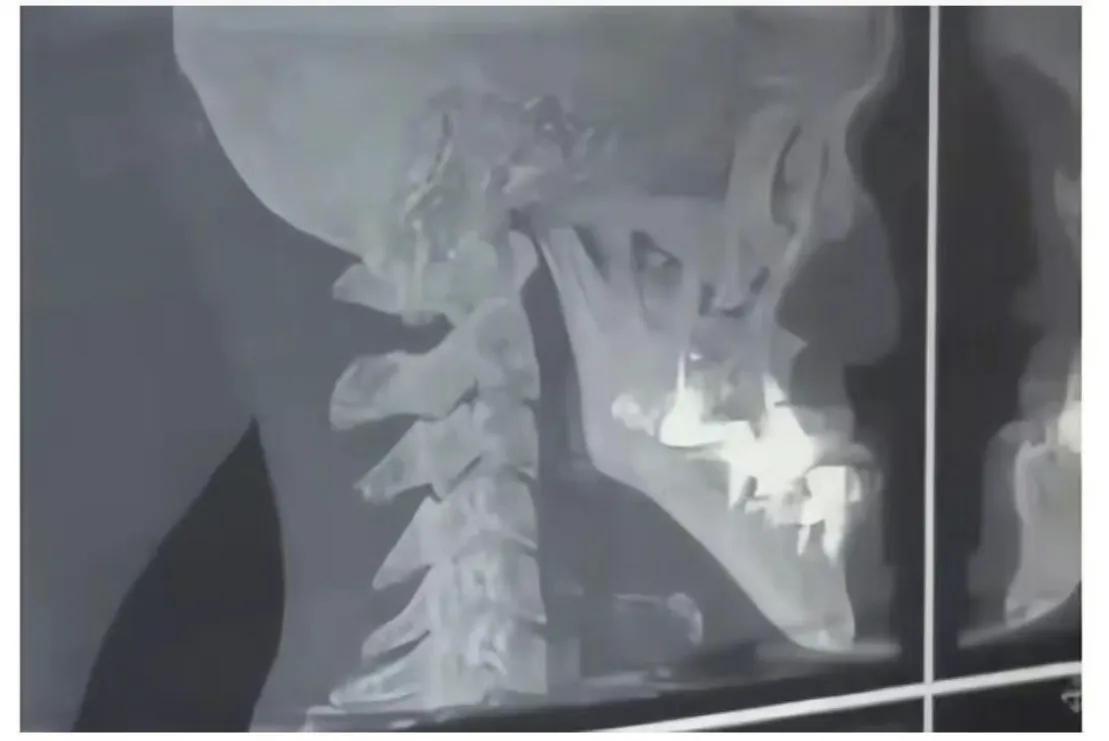

医生又认为是牙齿和骨骼问题,结果拍片发现城之内一切正常,这就让人百思不得其解了。

片子正常

城之内牙齿没有问题,只是单纯的下巴过长。